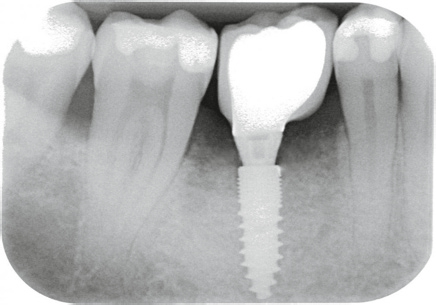

Ob Champions Zirkon-BioWin! (Abb. 9) oder Titan (R)Evolution Implantat (Abb. 11): Das aufbereitete Grinder-Zahnmaterial (Abb. 10) wird beim internen, direkten Sinuslift (IDS) erfolgreich, minimal- invasiv (MIMI Vb) und ohne Komplikationsgefahr mit abgerundeten Condensern und mit linksdrehendem, abgeflachtem 3,7 mm D Krestalbohrer unterhalb der Membran eingebracht.

Der („unblutige“) IDS benötigt nur wenige Minuten. Auf den Kontrollröntgenbildern sieht man deutlich „die Wolken“ des Grinder Materials, welches definitiv zu Knochen umgewandelt wird.